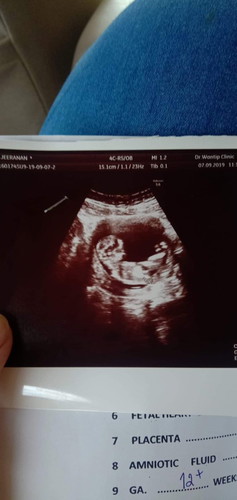

มีเเนวจะไปทางผู้ชายไหมน้ะ อิแม่ล่ะลุ้น เหมือนมีอะไรโพล่ๆ แม่ๆสังเกตเห็นเหมือนกันไหมค้ะ หรือแม่บ้านนี้คิดไปเอง จะไปซาวเพศน้องเดือนหน้าค่ะ แต่แม่ลุ้นๆไปก่อน ???

ดูไม่ออกค่ะ ไม่ใช่หว่างขา 😄 ภาพซาวด์นี้มันเห็นช่วงข้างลำตัวน้อง

รูปนี้ดูเพศไม่ได้เลยจ้า

กำลังตั้งครรภ์